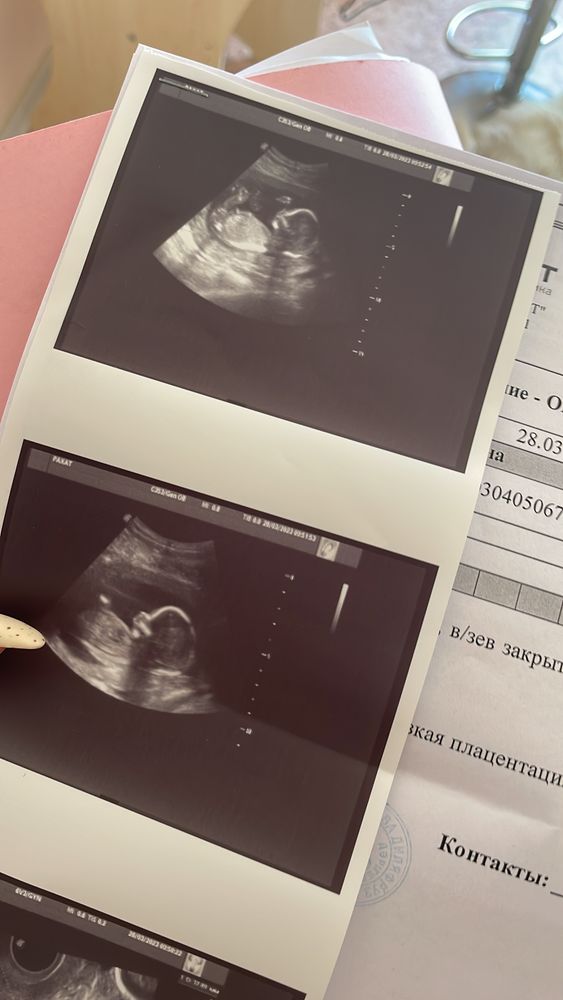

Так давно не писала, но поняла что это от того, что переживания наконец сменяются приятным ожиданием. Токсикоз наконец проходит, бывают эпизоды раз-два в неделю, но это уже прямо достижение. Снова начала пить витамины, полноценно питаться, ходить гулять, в общем - жить) очень-очень жду первых шевелений и пиночков. Вчера мерили шейку и заодно посмотрели пол, сегодня резали тортик, у нас будет ДЕВОЧКА😍 Муж, моя мама и брат, все говорили что будет мальчик, а я уже с 5 недели чувствовала, что девочка. На узи увидели низкую плацентацию, запретили секс, а у меня наконец появилось желание и влечение, вот блин😅 ждём пока плацента поднимется🙏🏻 иногда чувствую тревожность, боюсь что в какой то момент услышу что-то плохое, или скажут что нельзя самой рожать и тд, стараюсь бороться с ней, благо муж поддерживает. Наконец можно начать покупать и выбирать какие-то вещи, ой боюсь что все у нас будет в цветочек😁😁на следующей неделе предстоит лечить зубы, а еще нужно сделать циклоскопию глаз, посмотреть состояние сетчатки, так как уже была ранее операция, надеюсь там все ок🙏🏻 как-то сумбурно все выпалила, но очень хотелось поделиться потоком мыслей и эмоций. Оставлю фоточки моей беременности тоже тут)